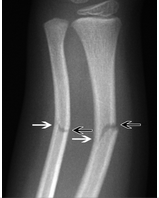

Dette er?

Klassisk greenstick-fraktur. Ofte å se i diafysen i lange rørknokler. Knokkelen gir etter på strekkesiden, der korteks ryker og åpner seg, mens på kompresjonssiden dannes en plastisk deformitet med intakt korteks. Må ofte reponeres ettersom den ulike involveringen av korteks på strekke-og bøyesiden av frakturen skaper en instabilitet som fører til feilstilling.